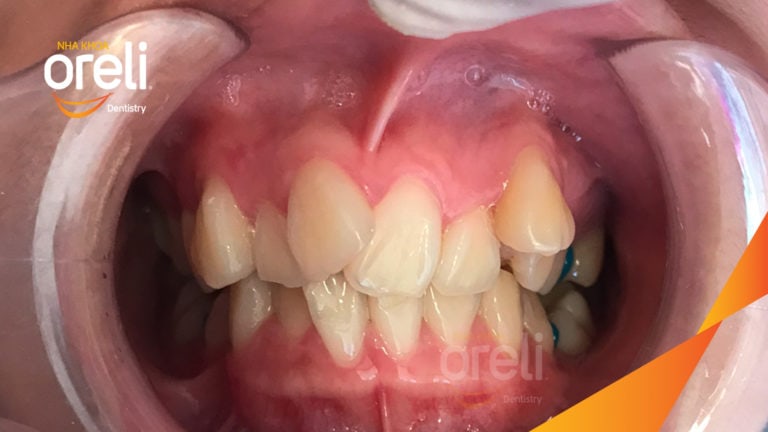

Ca niềng chỉnh chen chúc hẹp hàm nặng cả trên và dưới – Kết quả điều trị thực tế tại nha khoa Oreli Niềng răngChen chúc Xem thêm